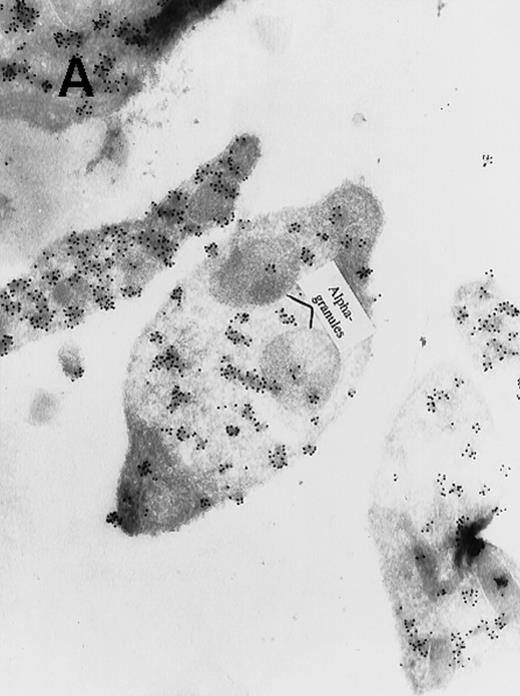

In view of these reports, we determined the cellular localization of MAP kinase in megakaryocytes, with a particular attention to the platelet-yielding demarcation membranes.7As a control, we determined the localization of another TPO-upregulated serine/threonine kinase, Mst1.8 Our current Electron Microscopic (EM) studies, performed as we described before,9 reveal that a significant fraction of MAP kinase, but none of Mst1, localizes to the demarcation membranes. In resting platelets, MAP kinase is found in a cluster pattern associated with the plasma membrane (which is believed to originate from the megakaryocytic demarcation membranes),7 as well as over electron-dense cytoplasmic domains (Figure). In view of our finding that MAP kinase is localized to the demarcation membranes in megakaryocytes, it is of interest to note that this kinase was also shown to be localized in Golgi membranes and involved in their fragmentation during mitosis in a microtubule-dependent manner.10 Platelet fragmentation likely involves the cytoskeleton, and perhaps MAP kinases are also involved in this process.

(A) Ultrathin frozen sections of rat platelets immunolabeled with antibodies to ERK (magnification ×45 000). (B) Well-developed demarcation membranes in a rat (Wistar), TPO-treated megakaryocyte7 9 immunostained with an antibody to Mst1 (magnification ×48 000), or (C) with an antibody to ERK, which recognizes ERK1 and ERK2 (magnification ×65 400). The arrows point to the demarcation membranes. The Mst1 antiserum (gift of Dr Jonathan Chernoff, Fox Chase Cancer Center, Philadelphia, PA) and anti-ERK2 (K-23) (Santa Cruz Biotechnology, Santa Cruz, CA) or TR2, anti-ERK (gift of Michael Weber, University of Virginia Medical School) were diluted 1:10.

(A) Ultrathin frozen sections of rat platelets immunolabeled with antibodies to ERK (magnification ×45 000). (B) Well-developed demarcation membranes in a rat (Wistar), TPO-treated megakaryocyte7 9 immunostained with an antibody to Mst1 (magnification ×48 000), or (C) with an antibody to ERK, which recognizes ERK1 and ERK2 (magnification ×65 400). The arrows point to the demarcation membranes. The Mst1 antiserum (gift of Dr Jonathan Chernoff, Fox Chase Cancer Center, Philadelphia, PA) and anti-ERK2 (K-23) (Santa Cruz Biotechnology, Santa Cruz, CA) or TR2, anti-ERK (gift of Michael Weber, University of Virginia Medical School) were diluted 1:10.